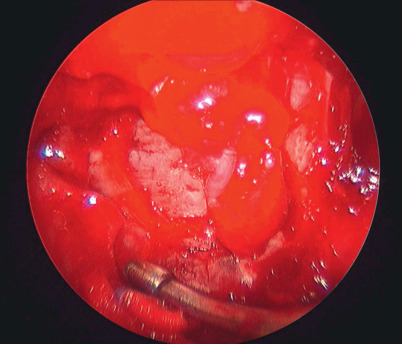

Endoscopic approaches through the maxillary sinus permit direct visualization and repair of the orbital floor and manipulation of the soft tissues without an eyelid incision ( Fig. 9.6 ) .

Figure 9.6

Endoscopic approach through the maxillary sinus permits direct visualization of the orbital floor and manipulation of the soft tissue and floor repair.